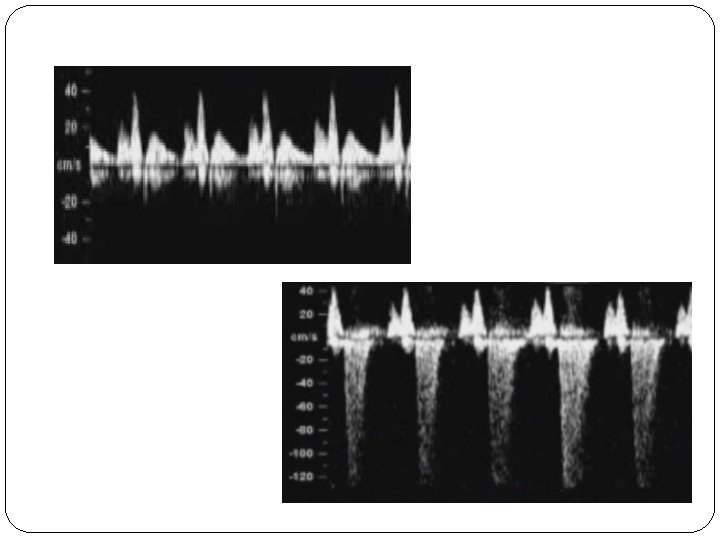

Hepatic Artery PI • After recording the DV flow, the sample gate can be slightly moved towards the descending aorta so that HA waveforms can be visualized (High-resistive flow)

Hepatic Artery PI • In trisomy 21 fetuses Increased flow in the fetal hepatic artery (Low-resistance flow)

� The hepatic artery (arrowhead) is seen as the vessel coming into close contact with the ductus venosus (*) and in continuity with the celiac artery, arising as the first anterior branch from the descending aorta. � The hepatic artery forms a triangle with the descending aorta and the ductus venosus.

Normal hepatic artery waveform of a 13 -week fetus. Abnormal hepatic artery waveform of a 13 -week fetus.

In fetuses with normal NT and normal outcome the mean HA-PI was 2. 03± 0. 46. In fetuses with normal NT and normal out-come DVPI 1. 07 at a CRL of 38 mm to 1. 00 at a CRL of 88 mm.